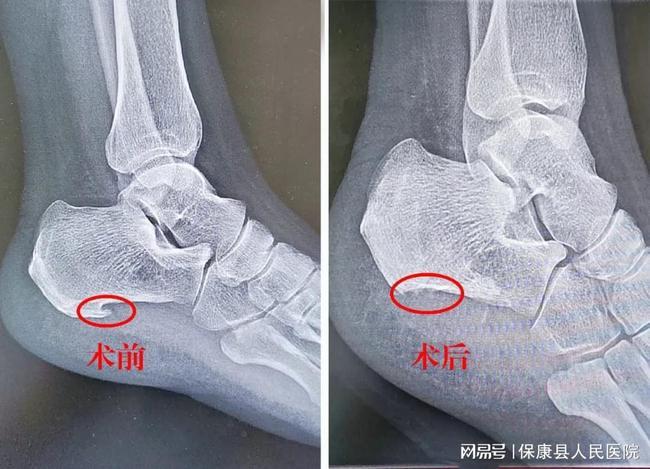

关节镜下切除跟骨骨刺治疗顽固性足跟痛

保康县人民医院成功开展首例关节镜下微创治疗跟痛症|骨刺|手术_网易